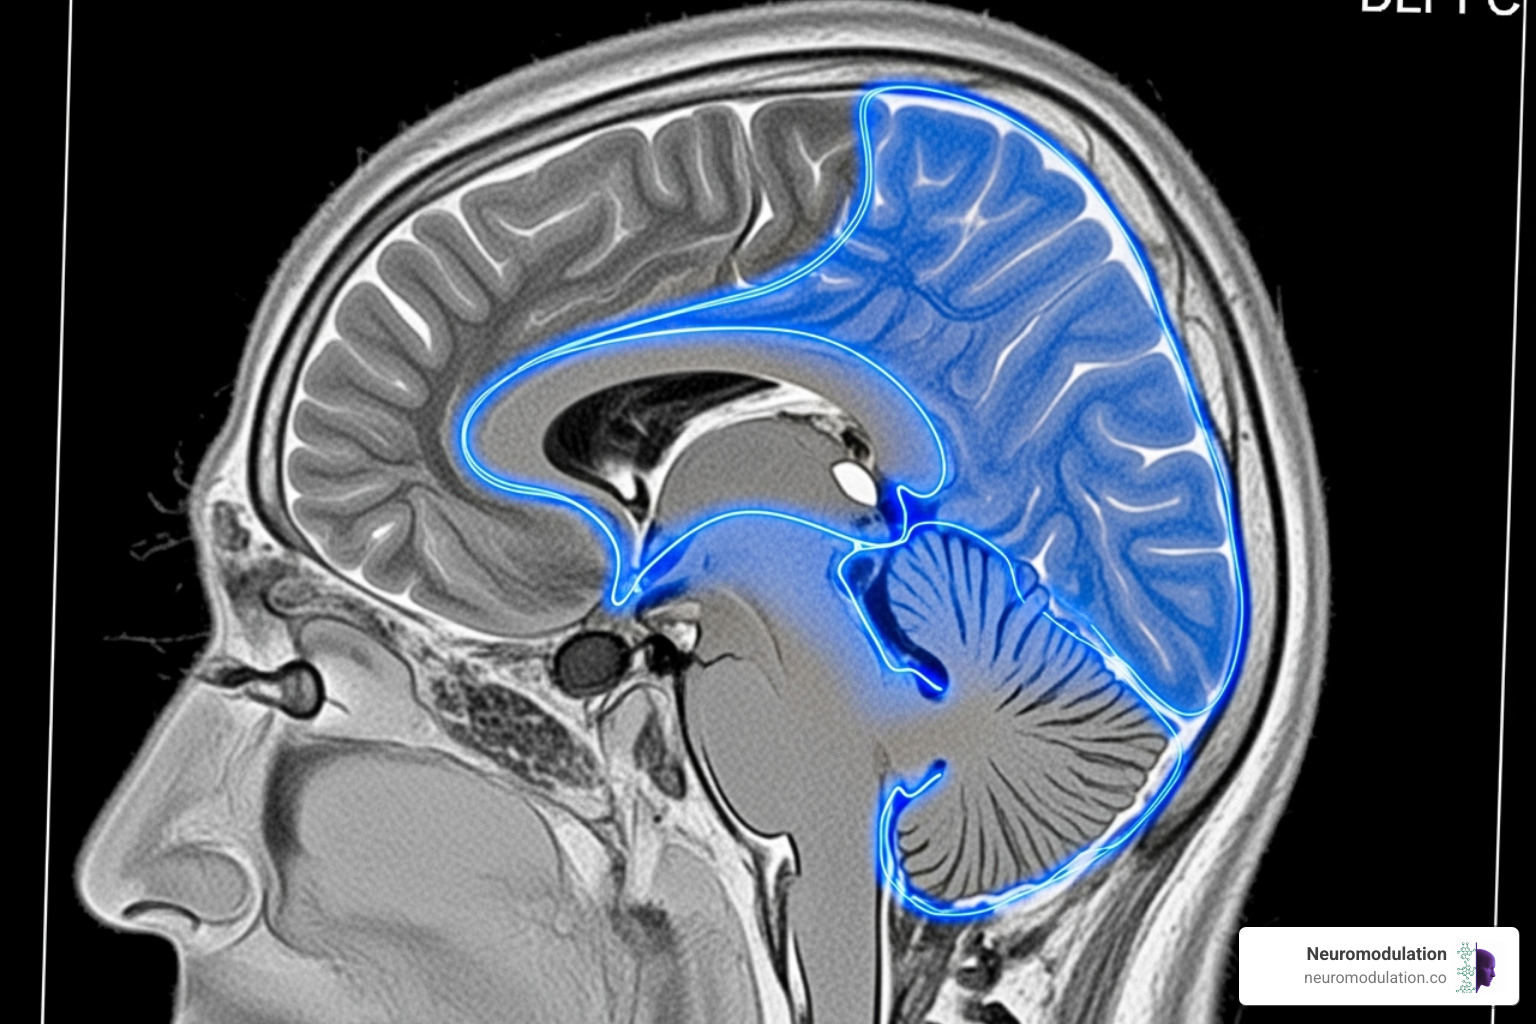

The primary target is the dorsolateral prefrontal cortex (DLPFC), an area involved in mood regulation and executive function. In depression, the left DLPFC often shows hypoactivity (reduced activity). High-frequency rTMS is used to stimulate this region, effectively “waking it up.” This approach is highly effective and widely recommended.

TMS also modulates interconnected brain networks:

- Default Mode Network (DMN): Often hyperconnected in depression, leading to rumination. TMS helps normalize this connectivity.

- Frontostriatal Circuits: Important for motivation and reward. TMS can trigger dopamine release in striatal regions, helping to restore the brain’s reward system.

- Limbic System: The brain’s emotional center, including the subgenual cingulate cortex (sgACC) and amygdala. Though TMS stimulates the brain’s surface, its effects propagate to these deeper structures to regulate emotion.

The ultimate goal is restoring network balance, shifting the brain away from maladaptive patterns toward healthier functioning. Scientific research on TMS and brain connectivity confirms that treatment leads to significant changes in these crucial circuits.